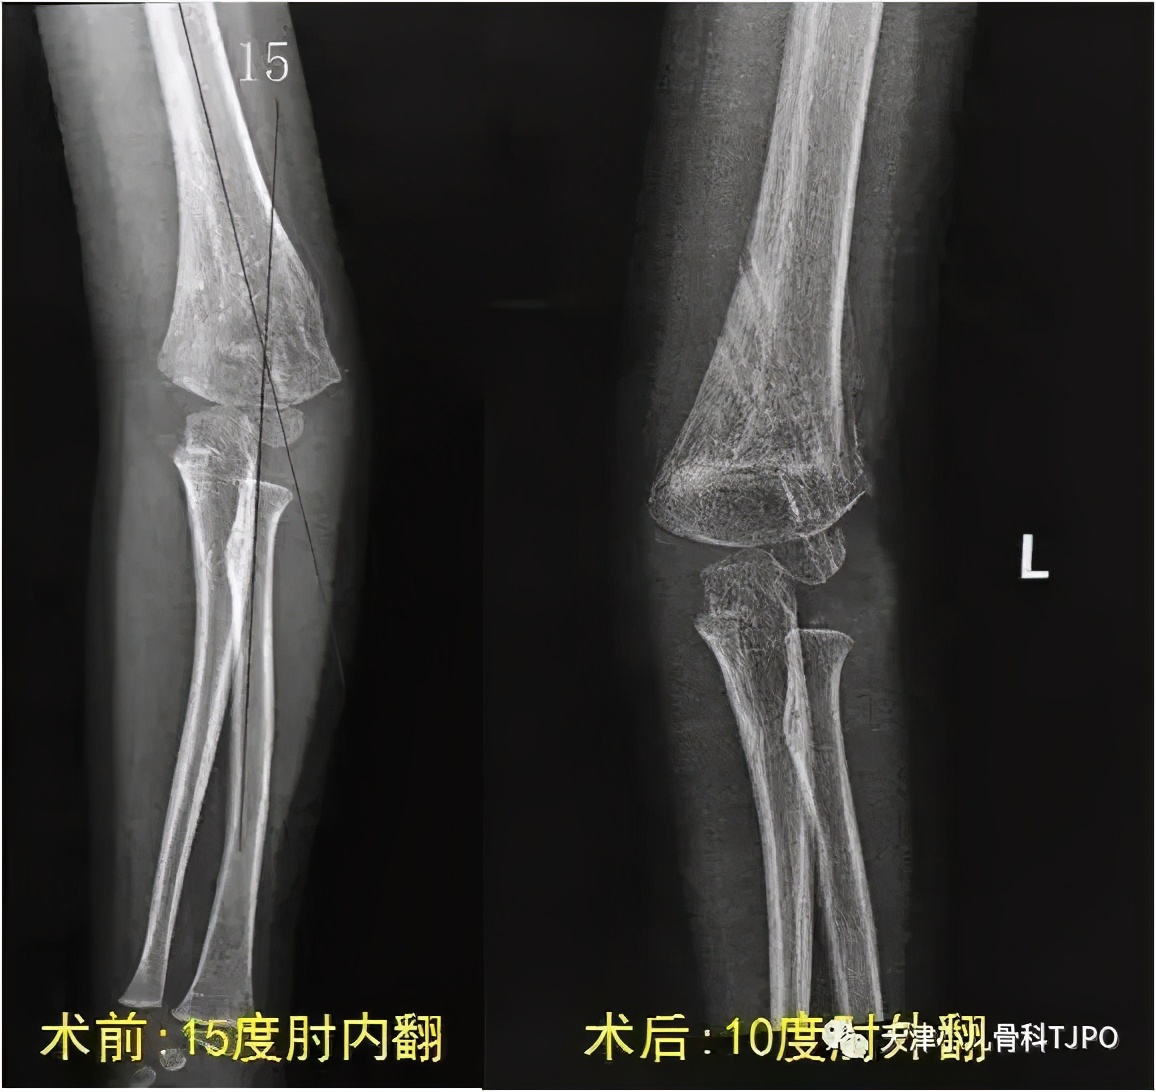

对于开始提到的女孩,我们通过双侧上肢片分析矫正角度后,采取“外侧闭合楔形截骨术”进行手术治疗,术后肘关节即可恢复正常轴线。手术微创,相对简单,刀口也是做美容皮内缝,术后通常需要石膏托固定,小孩子一般用克氏针固定即可,大孩子可以用外固定架或者钢板固定。

手术前后对比,可以看到这个孩子手术前有15度的肘内翻,手术后变成了和对侧一样10度肘外翻,外观和肘关节屈曲活动都恢复正常了。